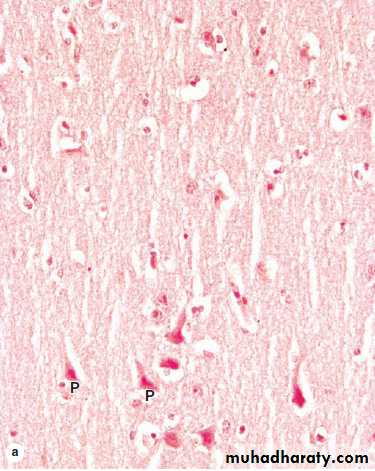

Cerebral Cortex